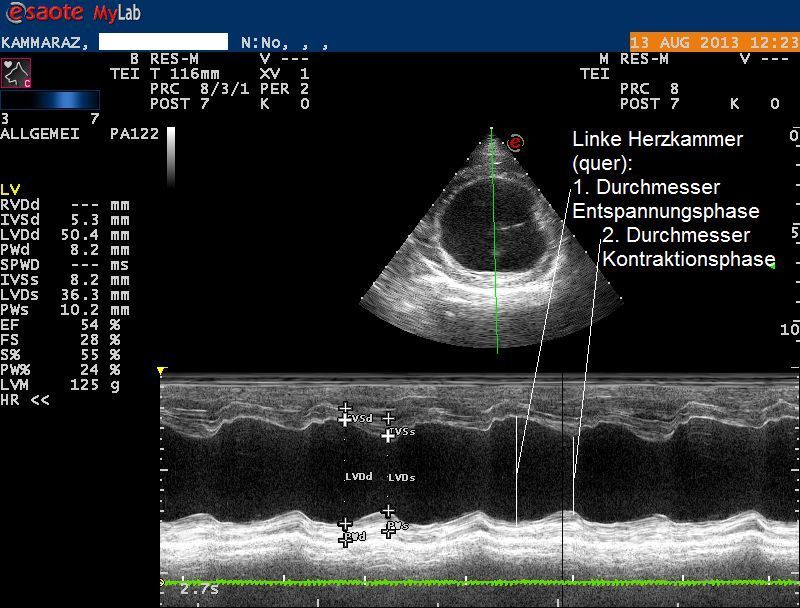

Weiterer Untersuch: Herzultraschall

Der Herzultraschall bestätigt den röntgenologischen Verdacht eines Herzproblems: Sowohl die Hauptkammer als auch der linke Vorhof sind bei Karammaz stark erweitert; die Kammer zieht sich ausserdem in der Pumpphase des Herzen zu wenig zusammen, wodurch das Organ zuwenig Blut fördern kann. Im Doppler-Ultraschall ist zu erkennen, dass durch die Erweiterung des Herzen auch die Klappen zwischen linkem Vorhof und linker Kammer undicht geworden sind und Blut beim Pumpen zum Teil nicht in den Körper, sondern zurück in den Vorhof gepumpt wird. Sonografisch ist also ein typisches Bild einer sogenannten Dilatativen Cardiomyopathie (DCM, Herzmuskelerkrankung, welche mit einer Erweiterung einhergeht) vorhanden; als Folge der geringen Pumpleistung des Herzen hat sich ausserdem ein Lungenödem gebildet.